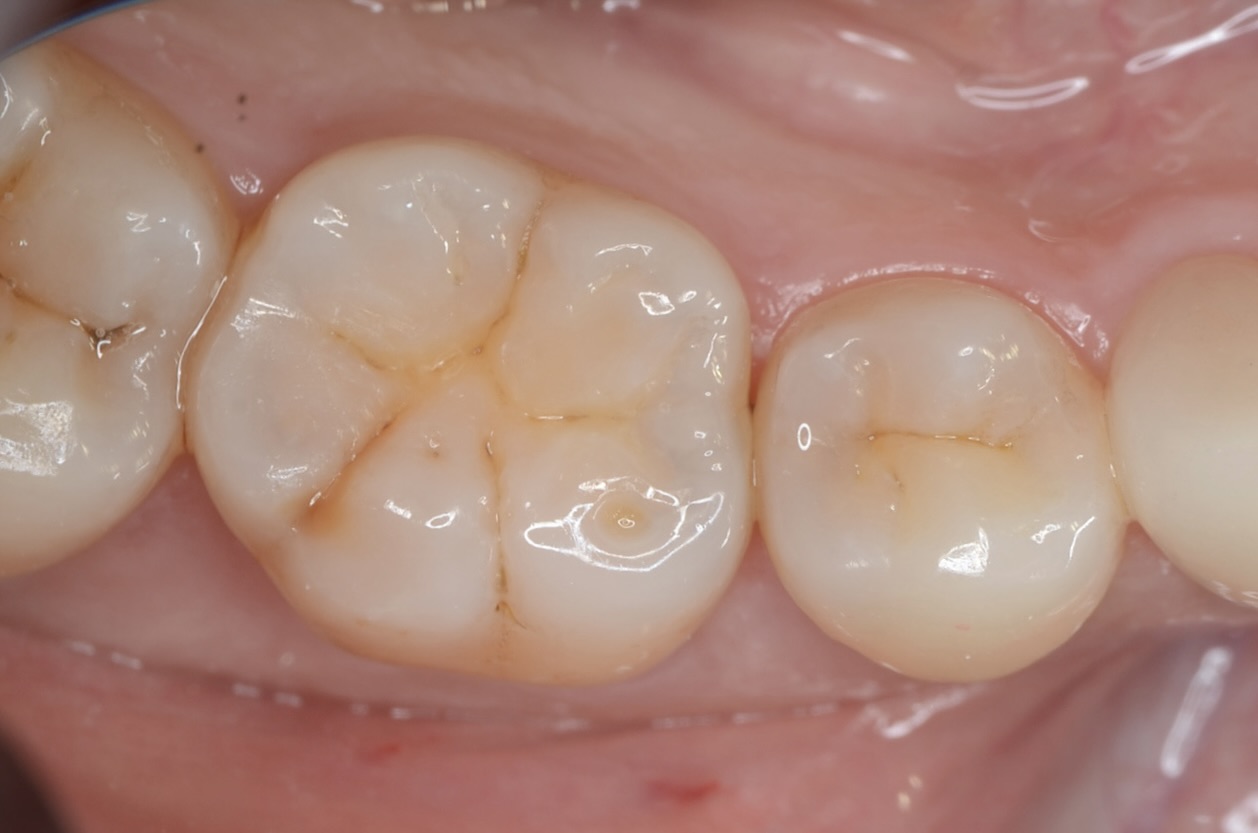

Before

After

| 年齢 | 40代 | 治療方法 | ダイレクトボンディング |

| 性別 | 女性 | 通院回数 | 2回 |

| 主訴 | できるだけ歯を削る量を少なくして,むし歯を治したい | 費用 |

121,000円(税込) |